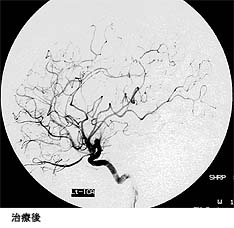

動静脈奇形部分に集中的に放射線を照射する治療法です。小型の病変が治療対象となります。サイバーナイフ治療の前後のMRIと血管撮影の画像を下に提示します。